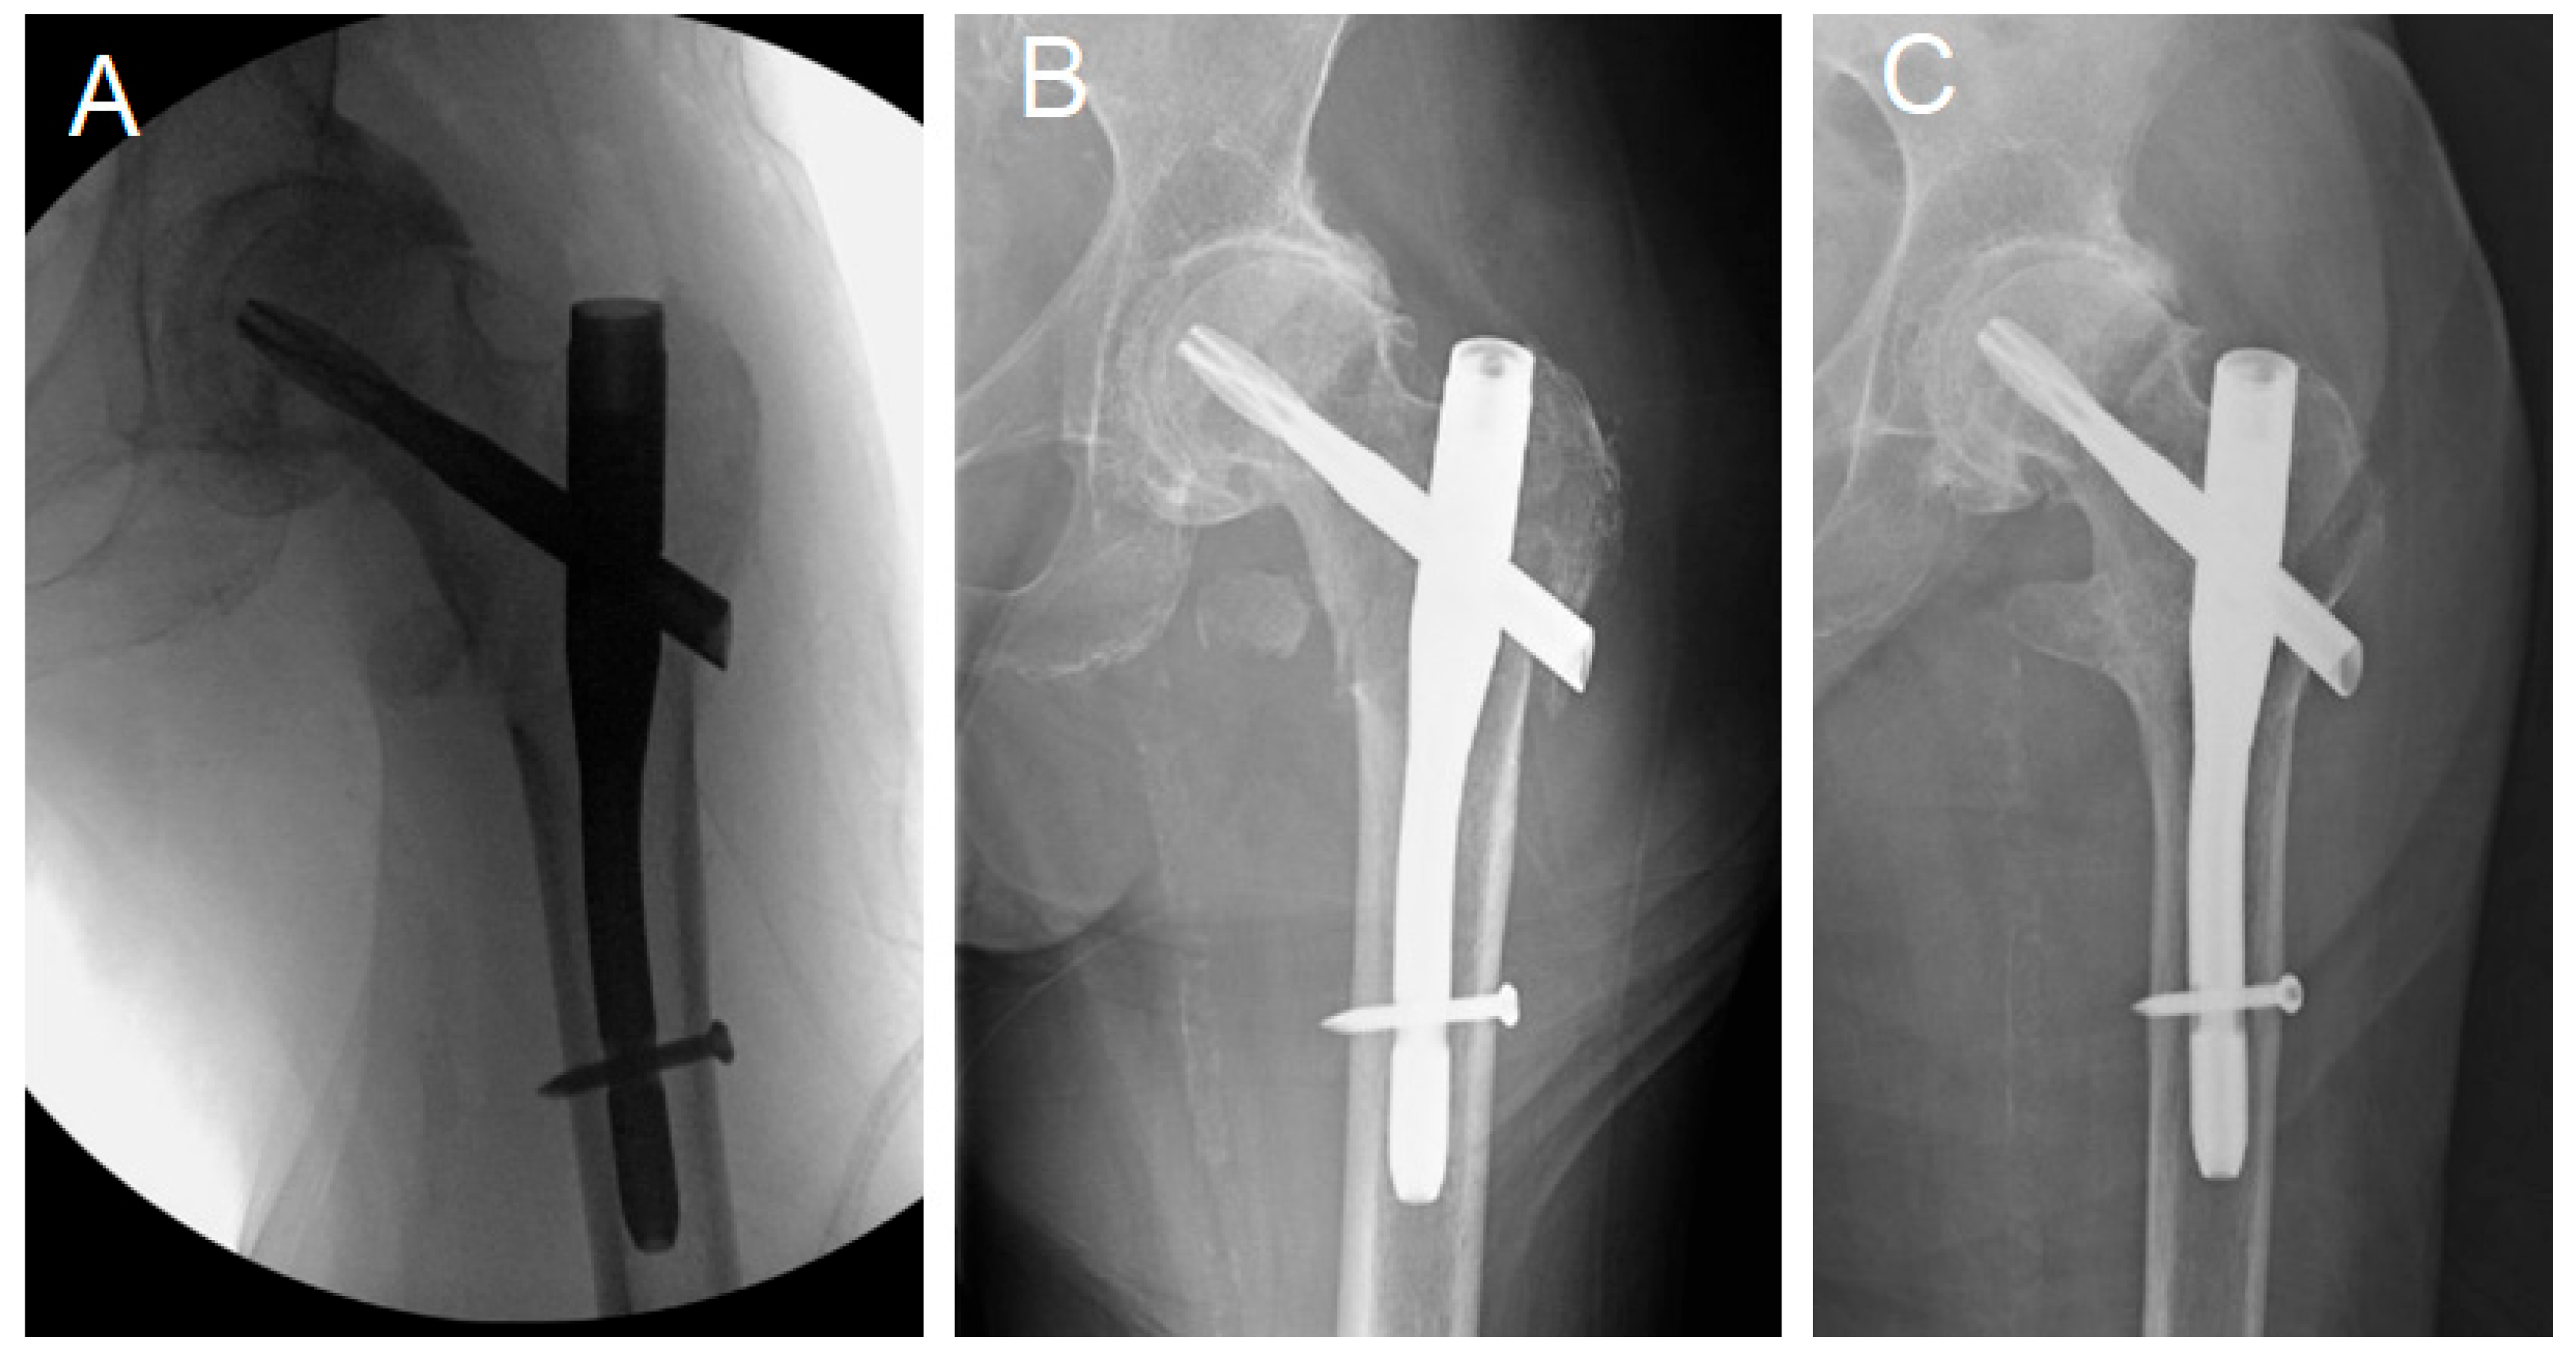

- Nail/femoral canal angle. Cases with significant toggling, as defined by George et al. [17] as a change in the nail/femur angle of more than 4 degrees, were documented.

- Distance between the medial tip of the distal end of the nail and the endosteal border of the lateral femoral cortex.

- Engagement of the lateral aspect of the lag device past the lateral cortex. A lag device was identified as “engaged” when both the superolateral and inferolateral borders of the device protruded freely outside the lateral femoral cortex in the intraoperative radiographs. This measurement was particularly made in the intraoperative radiograph to document the status of lag device engagement before any weight bearing and potential fracture collapse, to judge the utilized surgical technique.

- Integrity of the proximal femoral lateral cortex: The proximal femoral lateral wall, where the lateral end of the lag device engages, was assessed in the preoperative, intraoperative, and immediate postoperative X-rays or CT scan. Lateral wall incompetency was considered if any lateral wall breakage or fissure fracture was noticed.